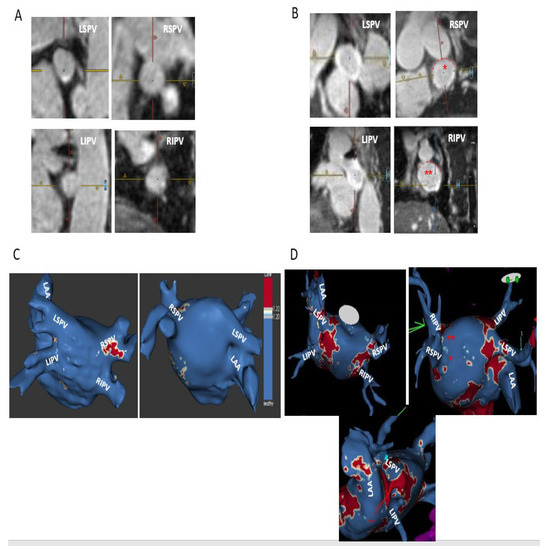

2.4. MRI Definitions and Categorization of Ablation-Induced PV Ostial Fibrosis

- −

- Complete—circumferential PV ostial LGE without gaps;

- Sub-complete—an almost circumferential LGE around PV ostium with the presence of a minor LGE gap only;

- Partial—incomplete circumferential LGE around PV ostium due to the presence of a major LGE gap;

- Absent PV fibrosis—no LGE around PV ostium.

) and thus are defined as partial incomplete circumferential PV ostial fibrosis. The right PV gaps are marked (

) both on the orthogonal plane images and the cross-sectional view.